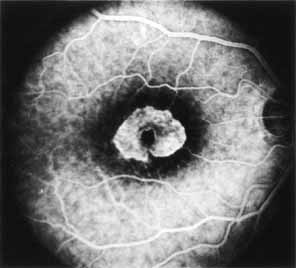

Although there is no reported genetic heterogeneity, there is wide phenotypic variation within the disorder. The major finding within the macula is a classic radial cystic maculopathy. Although retinal signs have been described in infants as young as 3 months, foveal schisis may be difficult to detect, leading to underdiagnosis. The diagnosis is usually not made until the affected male reaches school age (4 to 8 years of age) and encounters visual problems secondary to foveal involvement. Typical foveal schisis findings have been reported in 68% to 100% of eyes within various series.37,38 Foveal schisis is the only finding in about half the cases. It is characterized by the presence of radiate perifoveal microcysts located in the nerve fiber layer (Fig. 1) with radiate plications of the overlying internal limiting membrane that are seen especially well on monochromatic (red-free) photography (Fig. 2). The microcystoid change may slowly progress to form a macular cyst or hole. Foveal schisis has been reported in association with Goldmann-Favre vitreotapetoretinal dystrophy and rarely may be seen in rod-cone dystrophy or as an autosomal dominant or recessive condition.39–43